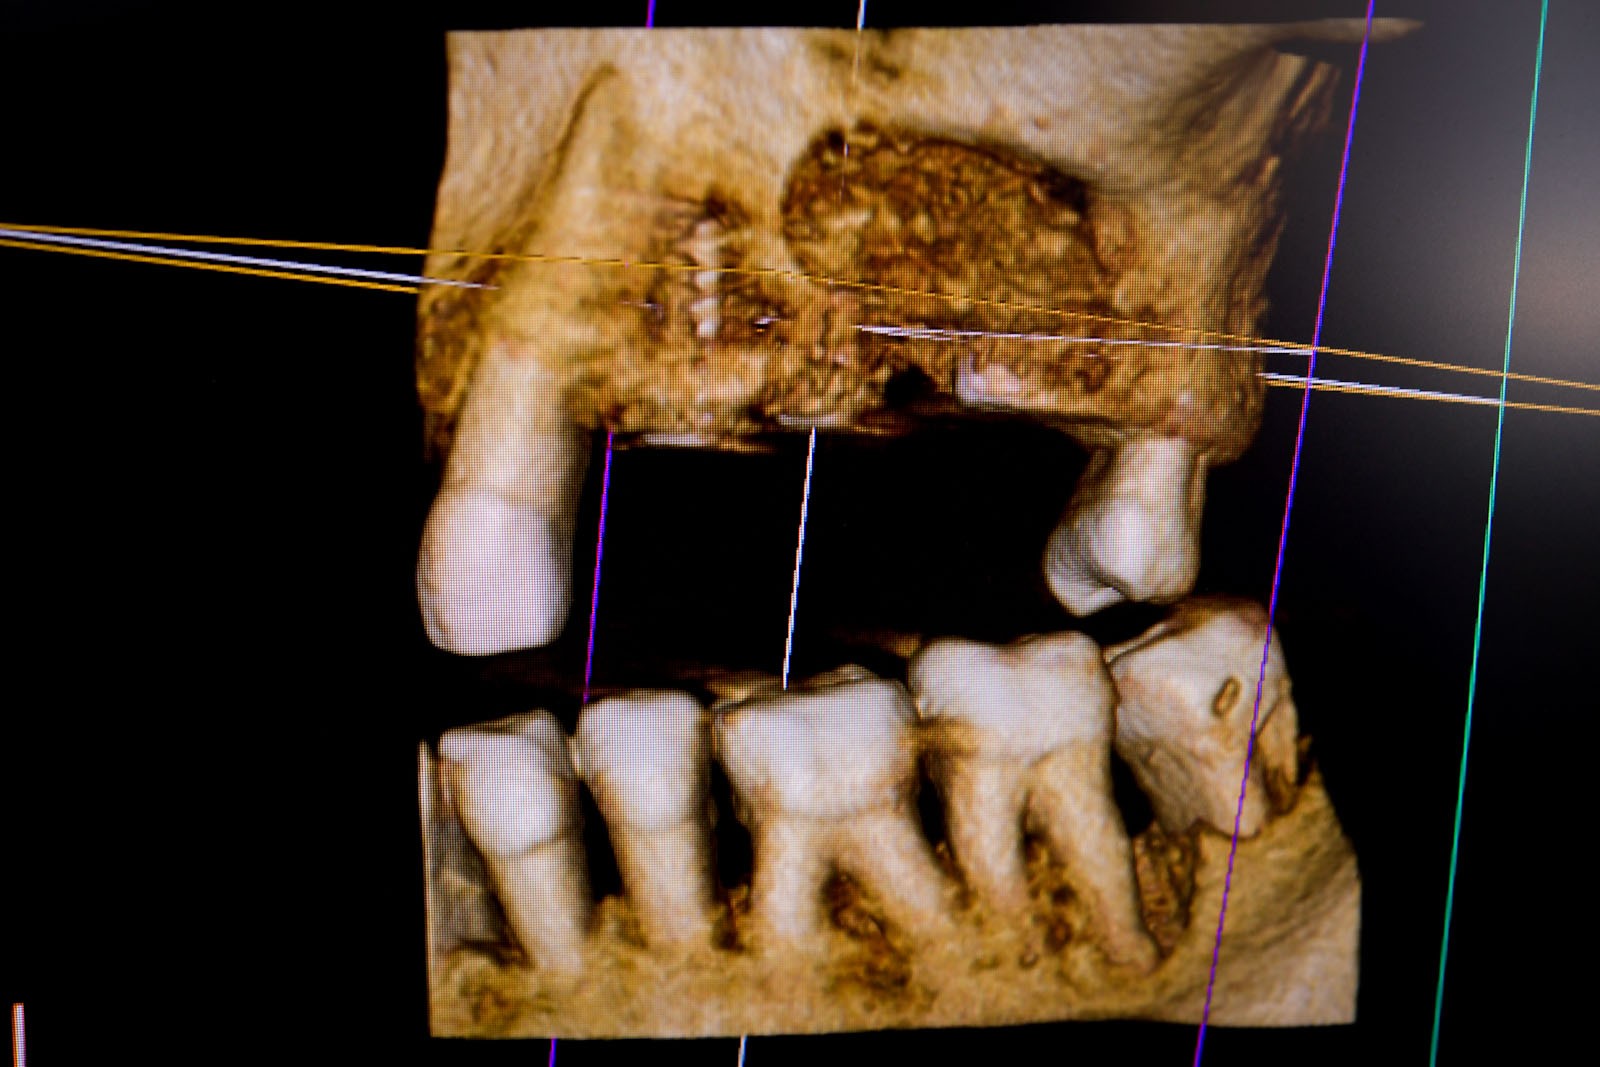

Przed podjęciem leczenia należy określić stopień zaniku kości szczęk oraz żuchwy. W tym celu przeprowadza się badanie kliniczne oraz odpowiednią diagnostykę obrazową pacjenta. Uwzględnia ona zdjęcie panoramiczne OPG jako podstawę dwuwymiarowego obrazowania podłoża kostnego oraz możliwe jest badanie tomograficzne CT lub bardziej precyzyjna tomografia stożkowa CBCT. Opcjonalnie wykorzystywana diagnostycznie tomografia pozwala na bardziej wnikliwą ocenę stopnia zaniku kości w trójwymiarowym, przestrzennym obrazie.

Precyzja projektu druku siatki bazuje na dokładności odwzorowania kształtu kości w stożkowej tomografii komputerowej CBCT, co zapewnia ich dobre przyleganie do podłoża kostnego oraz ogranicza powstawanie powikłań w postaci obnażania się siatek.

Ten rodzaj odbudowy kostnej stosowany jest w sytuacjach złożonych, trójwymiarowych 3D ubytków kości, przy których standardowe metody odbudowy są niewystarczające. Ilość kości, którą możemy uzyskać, stosując tę metodę, to nawet kilka centymetrów sześciennych.